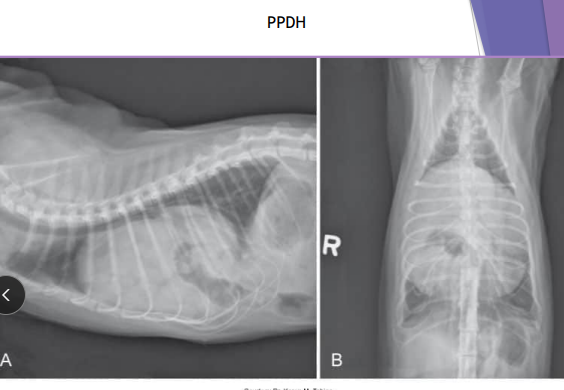

Diaphragmatic Hernia

Et: trauma, pressure gradient disruption, genetic

abdominal organs migrate into thorax, liver is #1

Peritoneopericardial d. hernia (PPDH) → congenital

Sig: Cocker spaniel, Weimaraner, Himalayan, DLH

Cs: shock(acute), dyspnea(chronic), exercise intolerance, ADR

Congenital is asymptomatic

Tears → weakest areas: muscle

Dt: thoracic rads (#1), US, CT

Tx: Sx (8-16w if congenital) (trauma: be ready for anything)

abdominal explore, identify hernia, reduce contents, close defect (absorbable 3-0 PDS, simple continuous, dorsal → ventral), remove air

Caution of adhesions

Do not close the pericardial sac (genetic)

Risk: re-expansion pulmonary edema, abdominal compartment syndrome, ARDS

Do NOT manually re-expand lungs, do not close pericardial sac